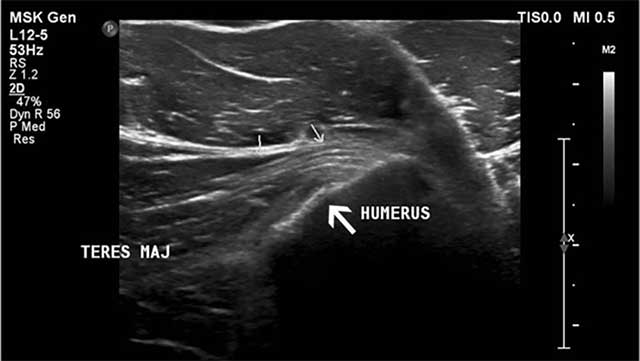

Figure 5

Ultrasound imaging (axial image) reveals an irregular delineation (large white arrow) of the teres major insertion at the medial aspect of the humerus posteromedial to the pectoralis major tendon (small arrows).